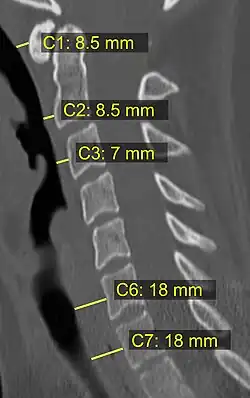

On CT scan or X-ray, a cervical fracture may be directly visualized. In addition, indirect signs of injury by the vertebral column are incongruities of the vertebral lines,[7] and/or increased thickness of the prevertebral space:[8]

X-ray of normal congruous vertebral lines